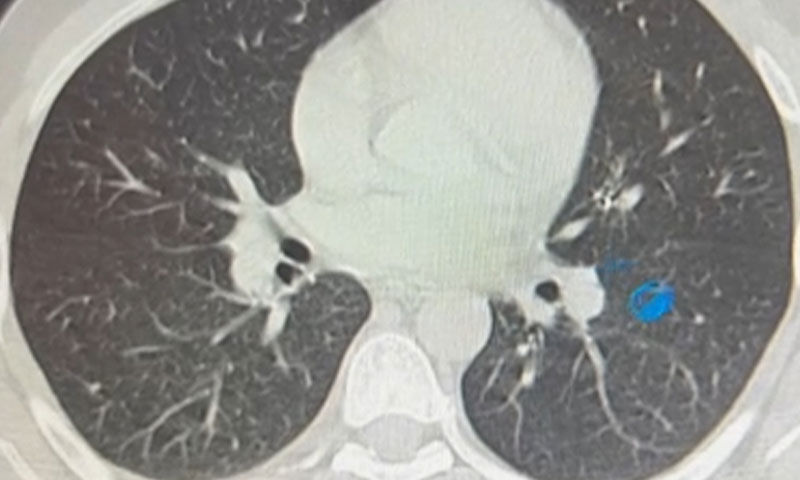

Konuya ilişkin konuşan Göğüs Cerrahi Op. Dr. Sadullah Aksoy, bir diş merkezinde diş tedavisi sırasında hastanın çenesine yerleştirilen implantın vida kısmının işlem esnasında yanlışlıkla aspire edildiğini belirtti. İlk olarak hastanenin ek hizmet binasında çekilen tomografi sonucunda, vidanın sol akciğerin hava yollarının yaklaşık dördüncü dalına kadar ilerlediği tespit edildiğini ifade eden Op. Dr. Aksoy, "Geçtiğimiz cumartesi günü öğle saatlerinde tarafımıza ulaşıldığında, hastanın Van Eğitim ve Araştırma Hastanesi'ne yönlendirilmesini istedik. Burada acil bronkoskopi planı yapılarak hasta kabul edildi. Hasta geldiğinde genel durumu iyiydi; solunumunu tamamen engelleyen bir bronş tıkanıklığı söz konusu değildi. Aynı gün hastamızı hazırladık. Bronkoskopi sırasında, implant vidasının sol üst lobun anterior segment bronşuna saplanmış pozisyonda olduğunu gördük. Üroloji bölümünde taş çıkarma işlemlerinde kullanılan cihazla müdahale ettik. İlk denemede implant tamamen çıkarılamadı ancak yerinden oynatılabildi. Bunun üzerine bir süre bekleyip hastayı yeniden bronkoskopi için hazırlamaya başladık. İşlem yaklaşık 3,5-4 saat sürdü ve saat 18.30 civarında hasta işlemden çıkarıldı" dedi.